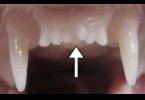

2 年前 - 日本一家名為ToregemBiopharma的新創製藥公司正研發讓新牙自然重的藥物。他們的科學家團隊研發了一種具有刺激牙芽生長能力的藥物,目標是在2030年左右將其推向市場。值得一提的是,這家公司得到了京都大學的資助,並計劃於2024年7月左右開始對健康成年人進行...